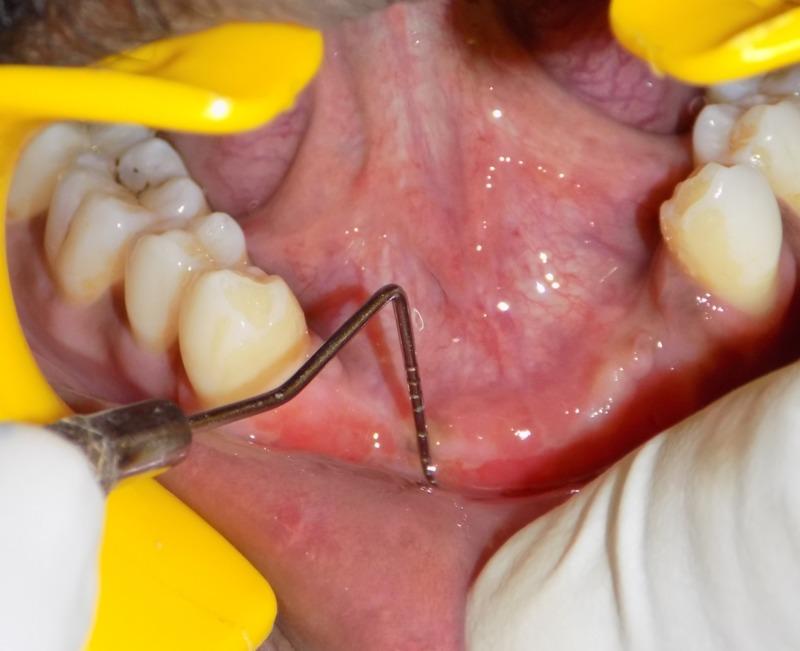

固定修复干预中附着龈减少的浅前庭管理

Management of Shallow Vestibule with Reduced Attached Gingiva in Fixed Prosthetic Intervention.

Shallow vestibule has long been considered a deterring factor in the use of removable dental prosthetics. The need for management in fixed prosthetic replacement is not widely discussed. Adequate attached gingiva is essential for continued proper oral hygiene. Muscular and fibrous traction leads to gingival recession, which can cause marginal leakage in a fixed prosthetic restoration. In the long-term, this causes the suprastructure to fail and, ultimately, the restoration also fails. Therefore, shallow vestibule with reduced attached gingiva should be identified in the diagnostic stage and should be effectively managed prior to restoration of lost tooth structure. This case report discusses the management of a shallow vestibule in a LeFort I fracture with emphasis on a fixed prosthetic replacement.

摘要

浅前庭长期以来一直被认为是使用可摘义齿的一个阻碍因素。固定义齿修复中管理需求的讨论并不广泛。足够的附着龈对于持续保持良好的口腔卫生至关重要。肌肉和纤维的牵拉会导致牙龈退缩,这可能在固定义齿修复中引起边缘渗漏。从长期来看,这会导致上部结构失败,最终修复体也会失败。因此,在诊断阶段就应识别出伴有附着龈减少的浅前庭,并在修复缺失牙体结构之前进行有效管理。本病例报告讨论了LeFort I型骨折中浅前庭的管理,重点是固定义齿修复。